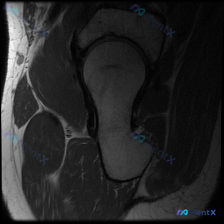

这个髋关节MRI结果为何没报盂唇病变?

看到一个髋关节MRI病例,患者怀疑有盂唇病变,但报告只说解剖正常。先放这张T1序列冠状位图像的解读,大家觉得盂唇病变的可能性大吗?

- 序列:T1加权,冠状位

- 部位:单侧髋关节

- 所见:股骨头、髋臼形态正常,骨皮质完整,骨髓信号均匀,关节间隙宽度尚可,盆周肌肉形态饱满,无明显异常信号灶。

- 为什么T1序列没发现盂唇病变?

- 进一步检查应该做什么?